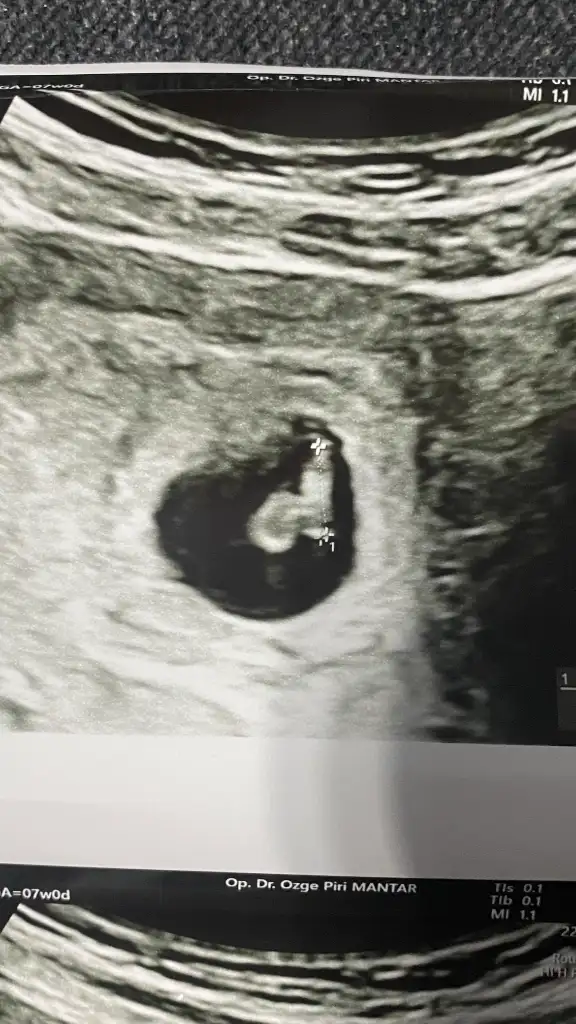

Bana da yorum yapabilir misiniz kızlar 7. Haftadan abdominal goruntu

• IMG_3201.webp

IMG_3201.webp

40,9 KB · Görüntüleme: 58

Abdominal görüntüyse eğer kız olabilir ☺️🌸 ama sanki sizin ultrason görüntünüz ters gibi . Normalde dar olan kısım yukarda geniş olan kısım aşağıda olur. Bilemedim bu bebişe karar vermek zor çünkü görüntü tam tersiyse eğer erkek de olabilir ☺️ sağlıkla gelsin. Daha net bir görüntü olursa paylaşın ☺️